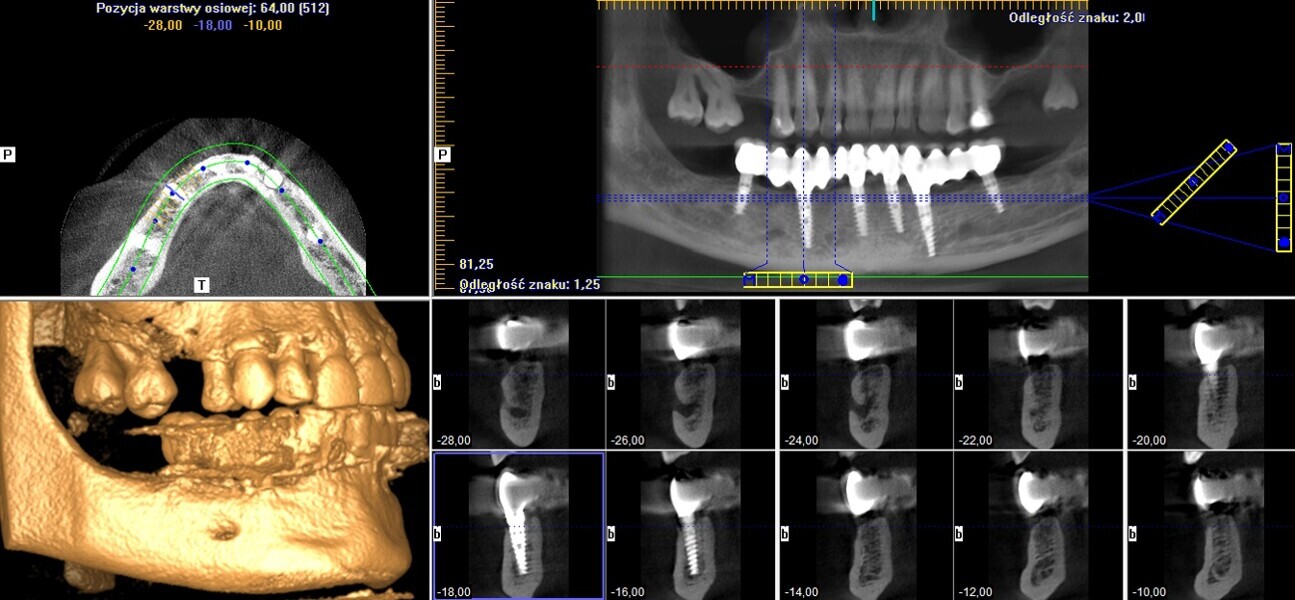

Natychmiastowa implantacja i zaopatrzenie protetyczne pacjentów z zaawansowaną chorobą przyzębia